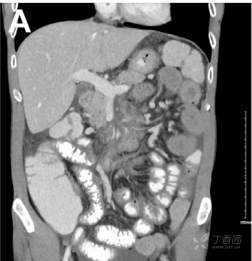

辅助检查:WBC16.2, Hb 118 g/L,PLT 278, CRP 41 mg/L 。大便检验提示沙门菌阳性,贾弟虫、艰难梭菌、诺如病毒及寄生虫卵均阴性。腹部增强所示如图A。.